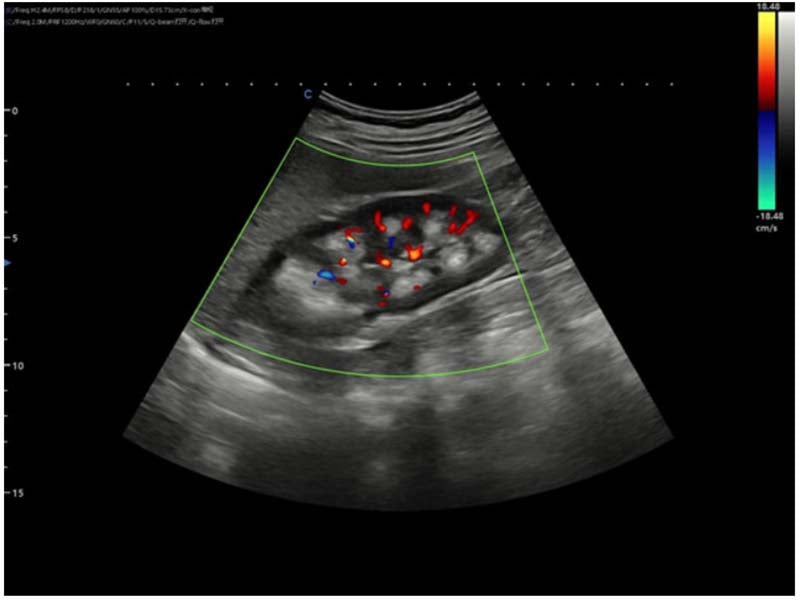

Ultrasound images

1. Renal cone echogenic enhancement: a strongly echogenic area with clear borders and radial rows.

2. Cone cystic structures: multiple anechoic areas of varying sizes are seen, mostly located in the papillary part of the cone.